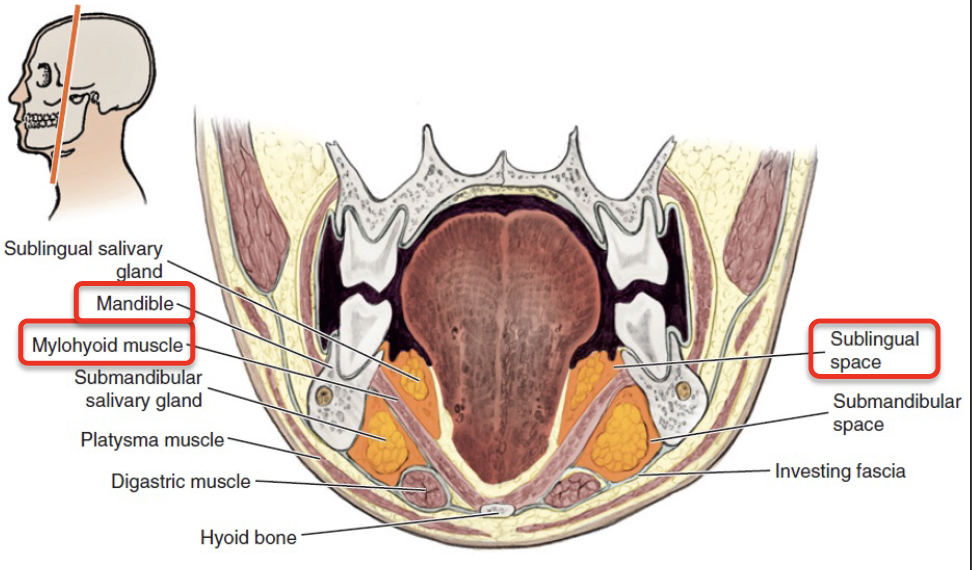

Space

Submental & Submandibular space

Submental

- Digastric, Hyoid bone, Mandibular symphysis 為界

- Superficial cervical fascia為底,Mylohyoid m. 為頂

Sublingual space

- Lingual n./a.

- Hypoglossal n.

Cervical spaces